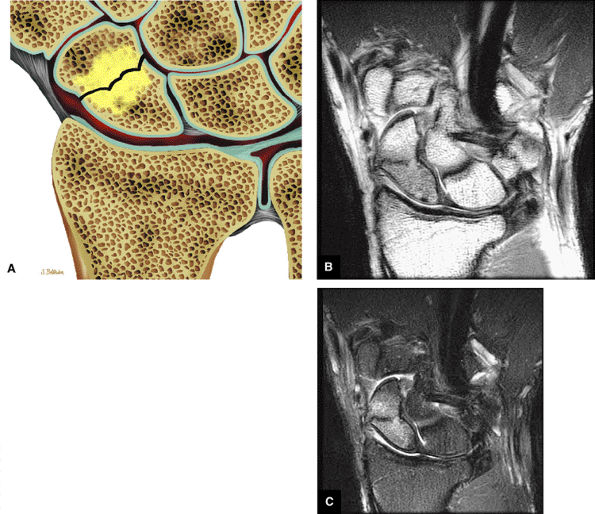

FIGURE 10.34 SCAPHOLUNATE LIGAMENT.

Fractures

However, a fluid-filled gap interposed between the membranous scapholunate ligament and the cartilage or bones should be interpreted as a perforation or detachment. Such membranous scapholunate ligament perforations and detachments are more common with advancing age (similar to tears of the TFC central disc), and in isolation may not necessarily result in carpal instability or significant symptoms. The volar-most images demonstrate the volar scapholunate ligament, which courses obliquely and attaches to bone on either side of the ligament. Tears of the volar and radial aspects of the scapholunate ligament suspected in the coronal plane can be confirmed in the axial plane. After identifying a scapholunate ligament tear, the scapholunate interval is assessed for widening, reactive bone marrow changes on either side of the scapholunate articulation, and bony or cartilaginous avulsions at the site of tearing or detachment. In addition, in the setting of scapholunate ligament tears, associated patterns of carpal instability, such as dorsal intercalated segment instability (DISI) pattern, can be identified on corresponding sagittal images.